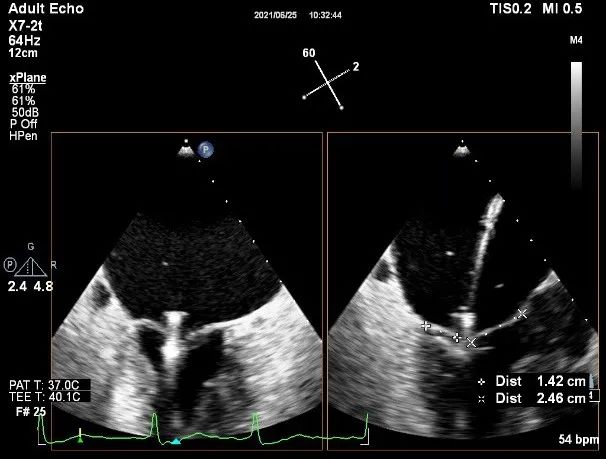

X-plane:下第夹子尝试捕获2区

X-plane:测量前叶长25mm,后叶长14.2mm

X-plane:计算前叶捕获长度8mm,后叶捕获长度7mm